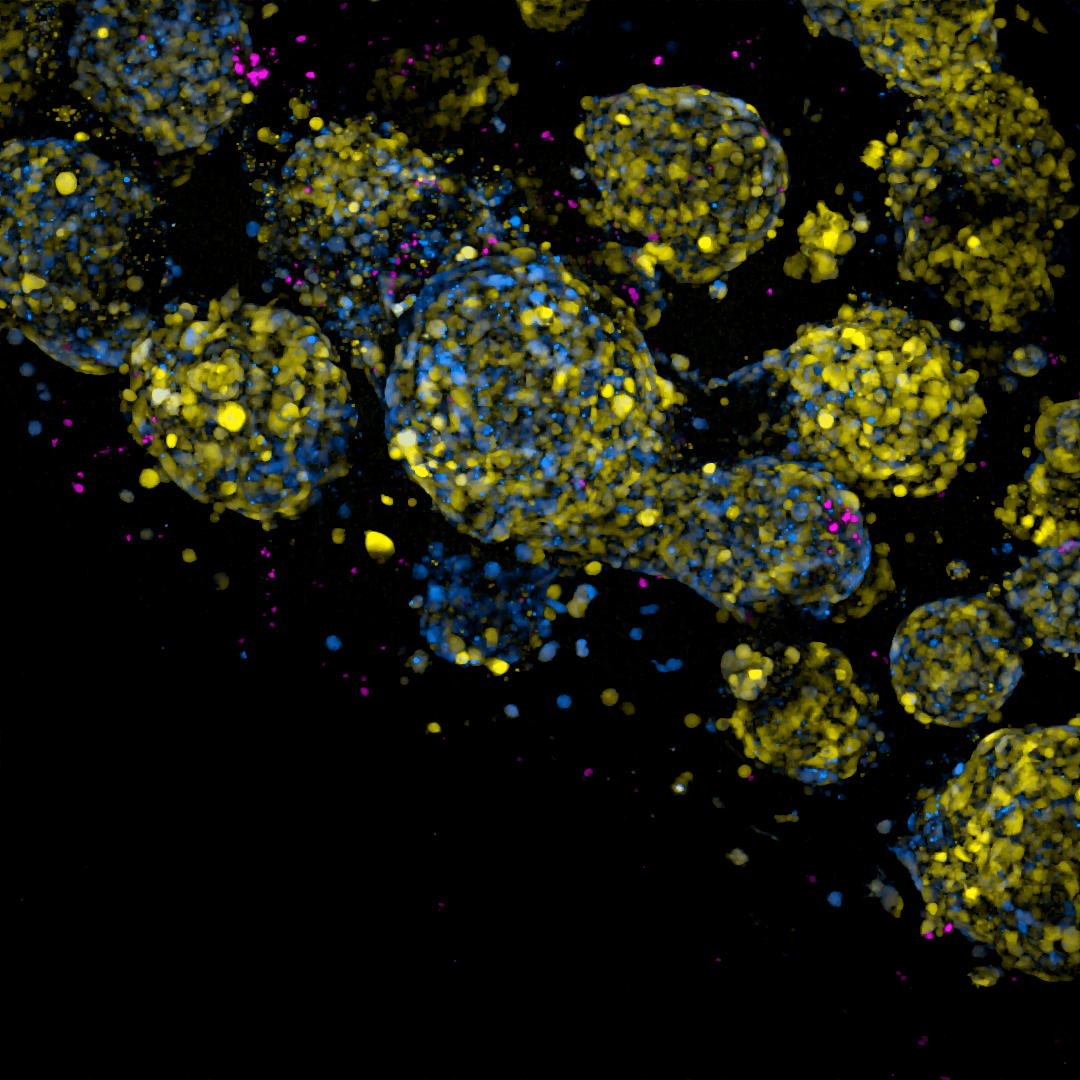

Das Team um Gargiulo will mit dem „Proof of Concept“-Grant des ERC ein neues Werkzeug konzipieren und testen, das die Qualität von T-Zell-Produkten aus dem Labor verbessern soll. Die Forscherinnen und Forscher nennen es SynT. Das synthetische Reportersystem soll verschiedene Zellzustände unterscheiden, die die T-Zellen entweder handlungsunfähig machen oder sie in einen kraftvollen „Serienkiller-Modus“ versetzen. Diese Zellzustände detektieren im Labor erzeugte DNA-Abschnitte, die jeweils ein fluoreszierendes Protein an- oder ausschalten (in der Fachsprache: synthetische Lokus-Kontrollregion oder sLCR). Je nachdem welche sLCR eingeschaltet ist, leuchten die Zellen unter einem Fluoreszenzmikroskop in einer anderen Farbe. Mit einem schnellen Mikroskop und einer Roboterplattform kann das Team Hunderte von Umgebungsbedingungen parallel testen und diejenigen finden, die den „Serienkiller“-Modus verstärken.